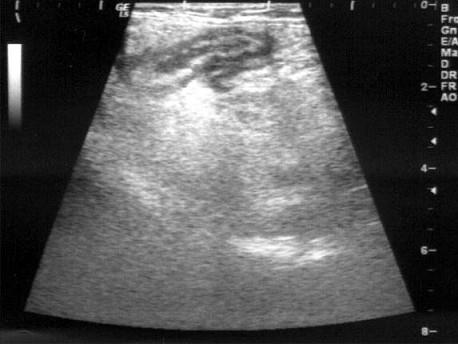

问题 患者男25岁,转移性右下腹痛1天。体检:右下腹叩击痛及反跳痛(+),血WBC1.3万,中性粒细胞82%。B超检查声像图如图所示,根据超声声像图,诊断为?(?)

选项 A.回盲部肿瘤 B.肠套叠 C.肠穿孔 D.急性阑尾炎 E.肠梗阻

答案 D